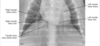

What view is this?

DV